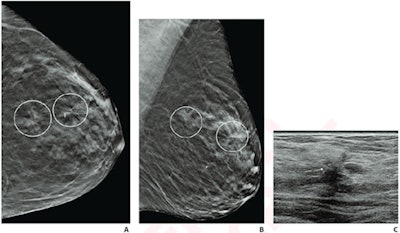

Researchers led by Dr. Lilian Wang from Northwestern Medicine in Chicago investigated DBT's utility in cases of women who have multiple ipsilateral or contralateral distortions on their scans. While these distortions could be an indication of a high-risk case, they might not necessarily be a sign of malignant disease, they said in a study published July 27 in American Journal of Roentgenology.

While research has shown that DBT detects more cancers and reduces recall rates compared with conventional mammography, the technology can also reveal subtle findings like architectural distortions that can present interpretation challenges. A 2021 study reported that such distortion on DBT has a pooled positive predictive value (PPV) for malignancy of 34.6%, suggesting that tissue sampling may be needed.

Therefore, Wang and colleagues wanted to compare pathologic outcomes between single and multiple architectural distortions identified on DBT.